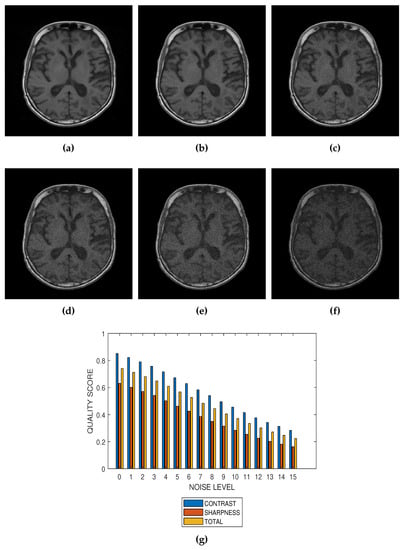

The first slice images (Figure 3a, Figure 4a, Figure 5a and Figure 6a) in Figure 3, Figure 4, Figure 5 and Figure 6 are the original images without degradation. The following five slice images are Rician noise degraded versions of the original images at Rician noise levels of 3 percent, 6 percent, 9 percent, 12 percent and 15 percent, respectively. For each level of noise, the contrast, sharpness and total quality scores are displayed in Figure 3g, Figure 4g, Figure 5g and Figure 6g. Expectedly, the quality scores decrease with increasing level of noise.

Figure 5.

(a) A conventional T1 weighted MRI slice from BrainCare Oy., and its degraded versions at Rician noise levels (b) 3 percent, (c) 6 percent, (d) 9 percent, (e) 12 percent and (f) 15 percent. (g) Variation of contrast, sharpness and total quality scores for Rician noise levels that vary from 0 percent to 15 percent.

The proposed method is a practical and realistic approach to quality evaluation. The images in Figure 3, Figure 4, Figure 5 and Figure 6 were evaluated without the need of a reference image. The images used for the performance evaluation were acquired with different levels of details and, hence, possess different perceptual quality. Variation in the profiles of quality scores shown in Figure 3, Figure 4, Figure 5 and Figure 6 shows that the proposed quality evaluation system can provide fairly good perceptual quality assessment for different types of MRI images.